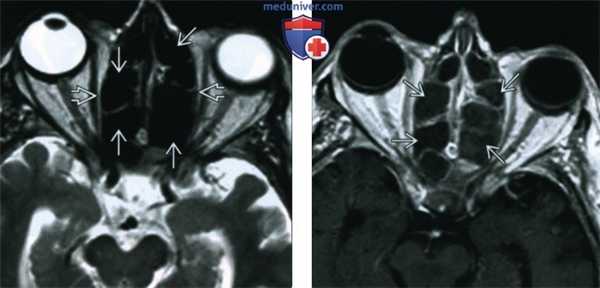

(Слева) При аксиальной КТ без КУ у пациента с диабетом и мукормикозом (ОИГРС) определяется циркулярное поражение правой верхнечелюстной пазухи с выраженными эрозиями задней стенки и замещением жировой клетчатки ретроантральной области и крылонебной ямки мягкотканным компонентом.

(Справа) При аксиальной МРТ Т1 С+ FS визуализируются фокальные неконтрастирующи-еся зоны в слизистой оболочке верхнечелюстной пазухи, соотносящиеся с некротическим струпом, жировая клетчатка ретро-антральной области и крылонебной ямки замещена мягкотканный компонентом.

(Слева) При корональной КТ без КУ у пациента с диабетом, почечной недостаточностью, жалобами на боль в глазу определяется снижение пневматизации левой верхнечелюстной пазухи, ячеек решетчатой кости с выраженным эктра- и интракональным ретроорбитальным мягкотканным компонентом, окружающим и смещающим внутреннюю и нижнюю прямые мышцы.

(Справа) При аксиальной МРТ Т1 определяется поражение решетчатой пазухи с чрескостным распространением в ретрорбитальные мягкие ткани. Была выполнена экзентерация орбиты, максиллэктомия, этмоидэктомия, подтвердился ОИГРС (Mucor).